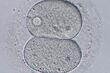

細胞分裂の様子

[写真 8/11枚目] 細胞分裂の様子